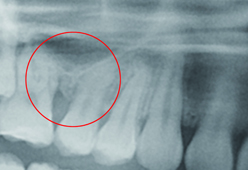

圖二、導航輔助齒瘤切除手術(來源提供:李慶璿醫師)

(左上)手術前,齒瘤纏繞鄰近牙齒的牙根。(左下)手術後,齒瘤完整摘除且鄰近的牙根完好無暇。(右)醫師手術中使用導航輔助摘除齒瘤手術。